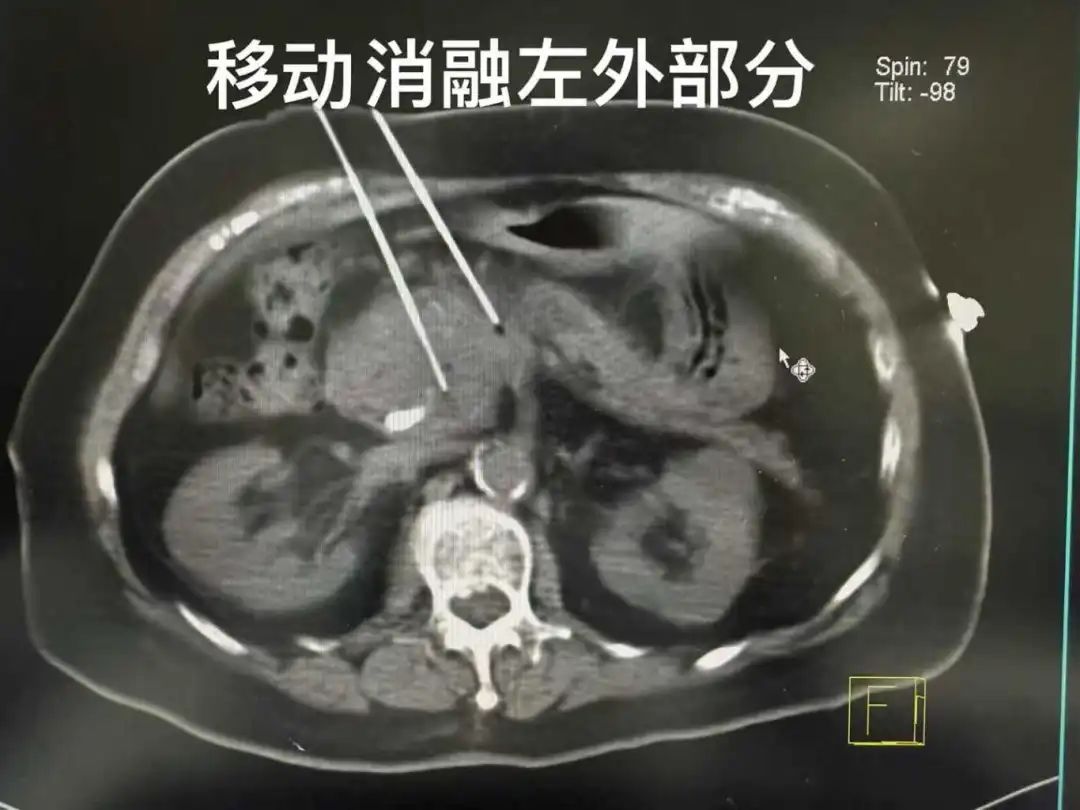

△来自菲律宾的胰腺癌患者,在当地不能手术行胆道支架植入后,专门来中国找我做纳米刀消融治疗!5.3cm的肿瘤位于胰头部,结构复杂,今天在超声联合CT下,采用移动消融技术,成功完成纳米刀消融。